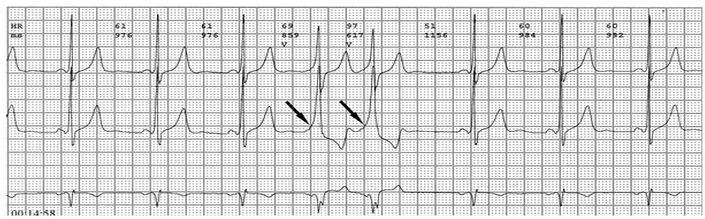

各旁路引起预激的心电图特征如下:

1、房室旁道

(1)PR间期(实质上是P-δ间期)缩短至0.12秒以下,大多为0.10秒;

(2)QRS时限延长达0.11秒以上;

(3)QRS波群起始部粗钝,与其余部分形成顿挫,即所谓预激;

(4)继发性ST-T波改变。

上述心电图改变尚有分为A、B两型的。A型的预激波和QRS波群在V1导联均向上,而B型V1导联的预激波和QRS波群的主波则均向下;前者提示左室或右室后底部心肌预激,而后者提示右室前侧壁心肌预肌。这种分类方法虽然受到预激是不同部位旁路所致的多变QRS波群的限制,但有助于区别旁路的心室端在左或右、前或后,因而沿用至今。

2、房结、房希旁道

PR间期少于0.12秒,大多在0.10秒;QRS波群正常,无预激波。这种心电图表现又称为短PR、正常QRS综合征或L、G、L(Lown-Ganong-Levine)综合征。

3、结室、束室连接

PR间期正常,QRS波群增宽,有预激波。预激综合征室上性心动过速发作时,预激表现大多消失,心电图表现为QRS波群形态正常的室上性心动过速。并发房扑或房颤时,QRS保持预激特征的不少见,心电图表现为QRS波群畸形宽大的房扑或房颤;心室率大多超过200次/分,甚至可达300次/分。房扑时可呈1:1房室传导,并可能辨认房扑波。房颤时心室律不规则,长间歇之后可见到个别QRS波群形态正常(可能为旁路不应期延长,房室结内隐匿传导作用消失后,冲动全部或大部经房室结传导所致),并可能辨认房颤波。心室率极快时,还可伴有频率依赖性心室内传导改变。